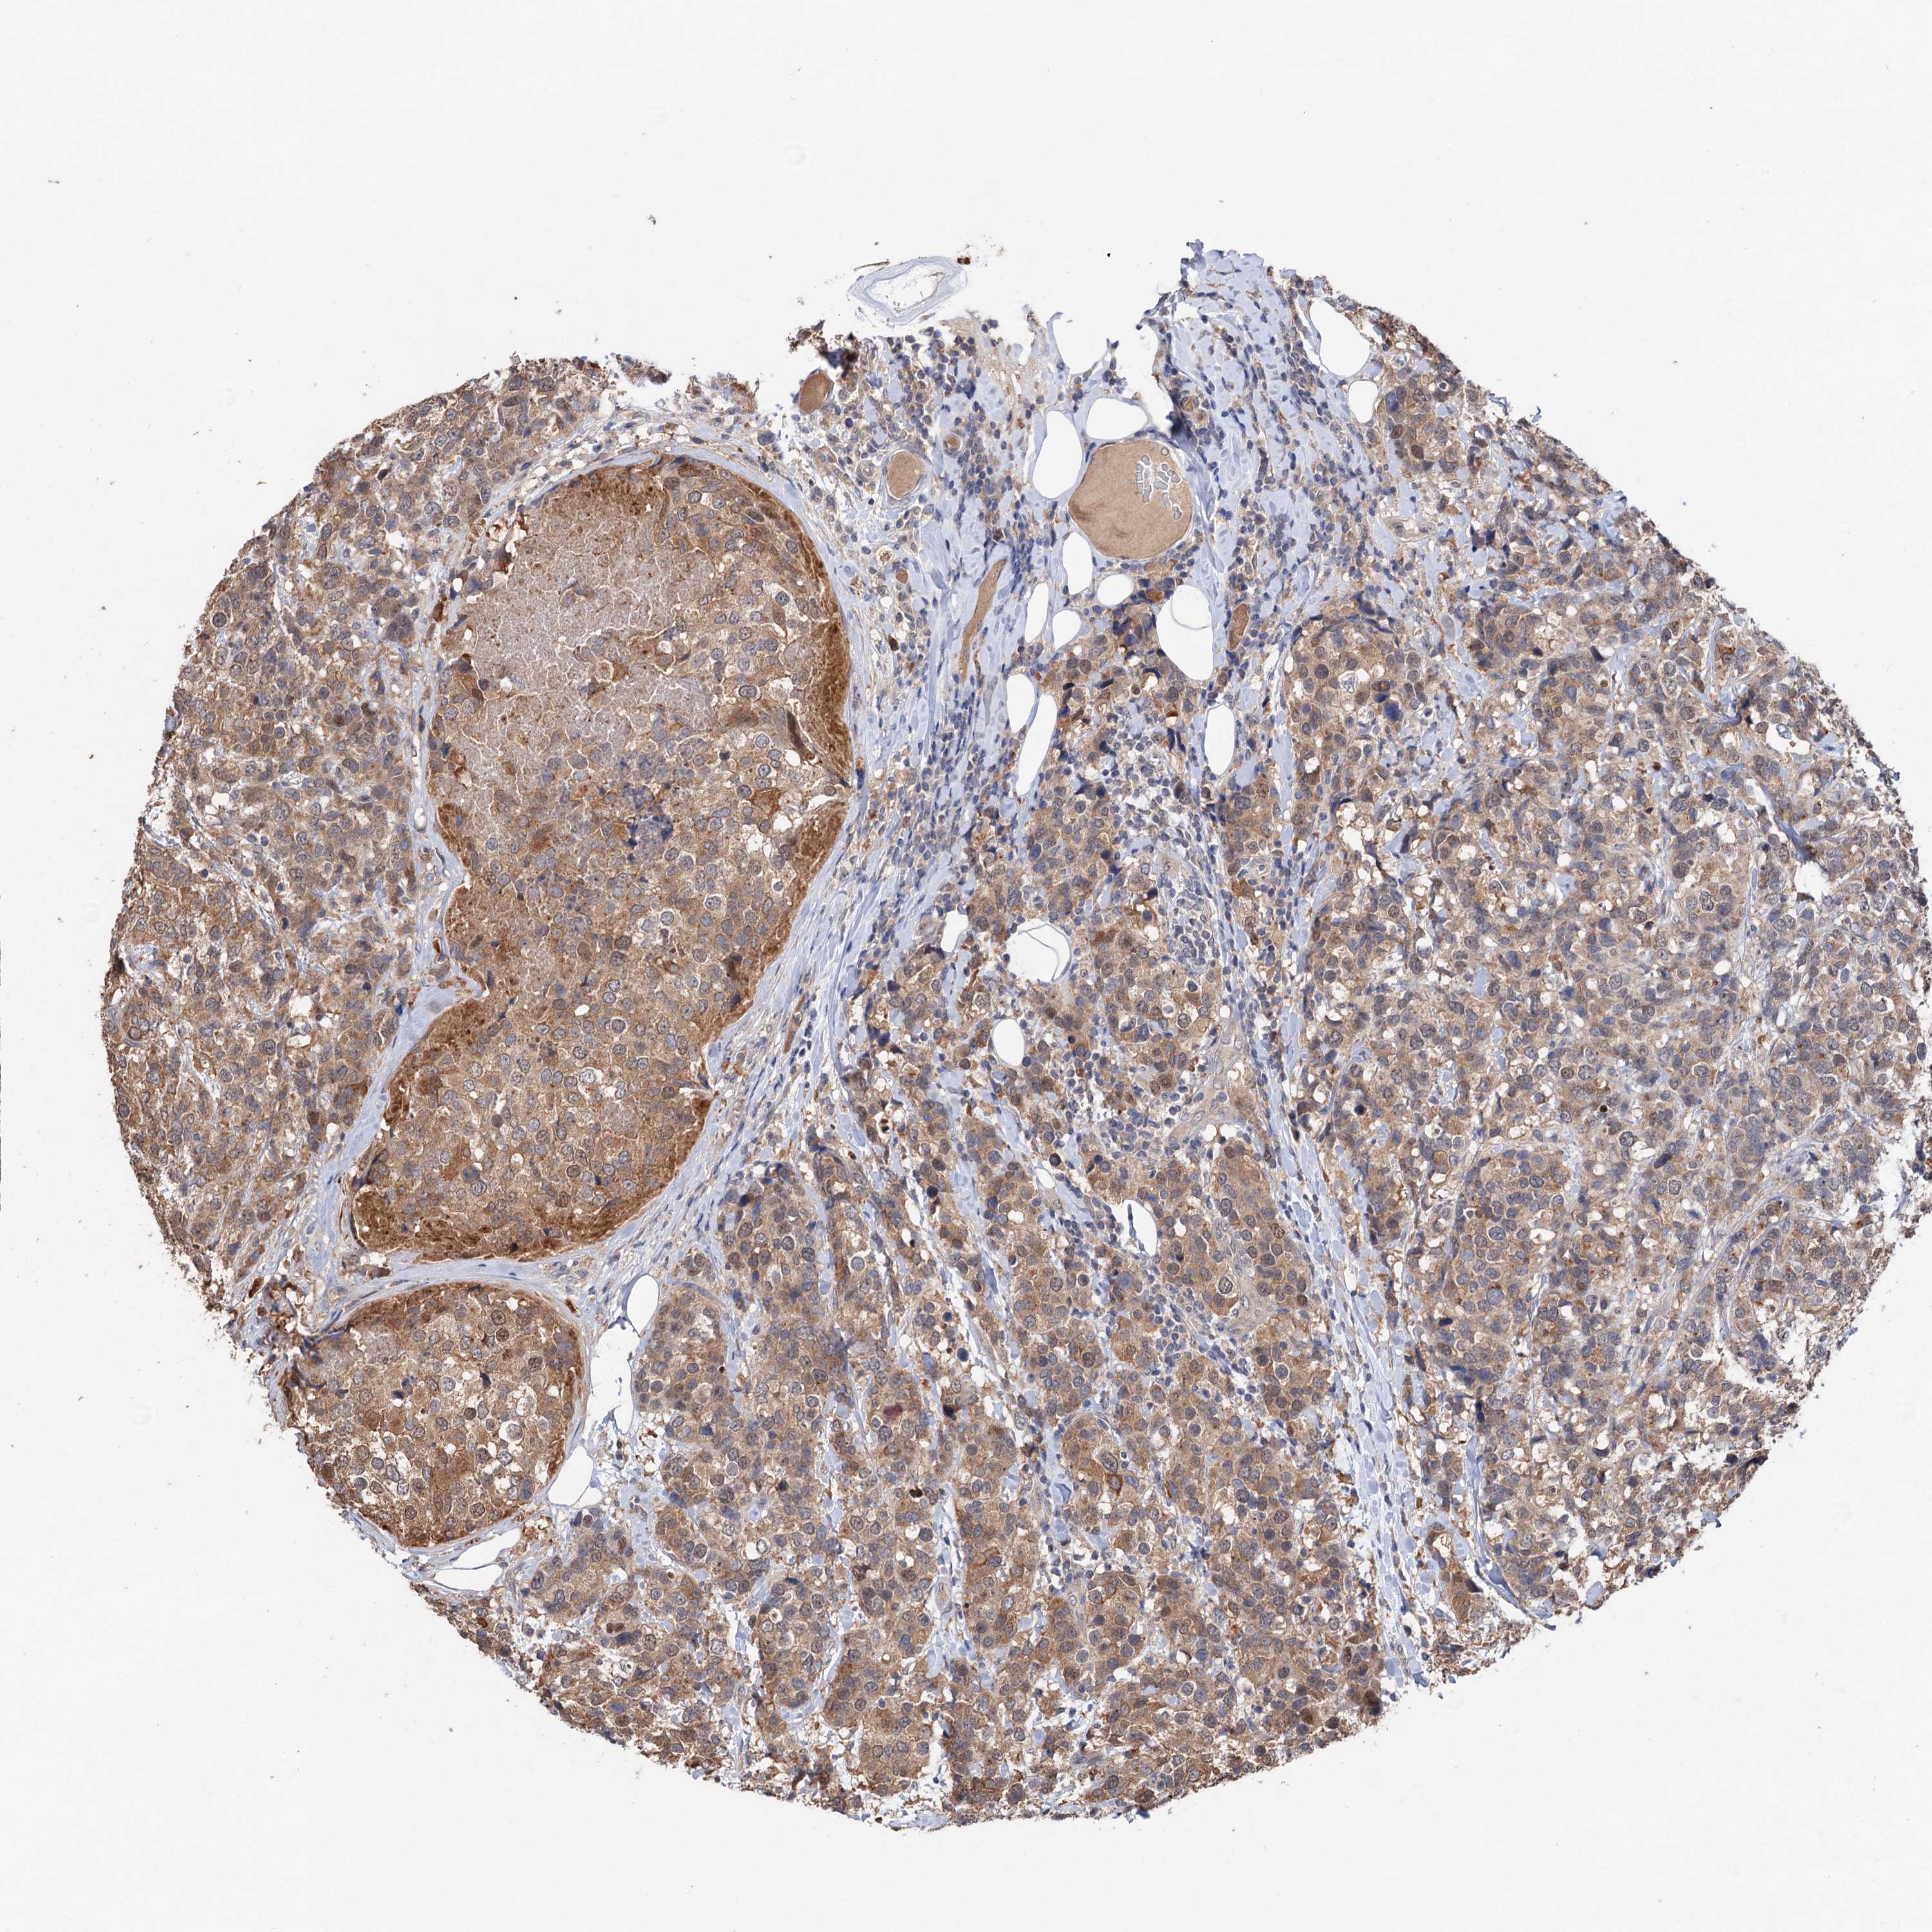

CANCER BREAST CANCER Show tissue menu

BRCA TCGA BRCA VALIDATION PROTEIN EXPRESSION